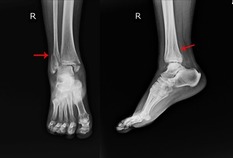

Podiatry Radiation Tech Registration Update

foot xray podiatrist

As of January 1, 2025, a podiatric medical radiological technician, or rad tech, registration is now issued or renewed for two years. If a registration was renewed in 2024, the registration period is still one year, but future renewals will be for two years. The fee for initial and renewal registration has been increased to $50.00, to reflect the expansion of the registration period.

Regarding those individuals registering for the first time, the minimum training hours and X-ray requirements increased beginning in December 2024.  Make sure the certificate you receive reflects those changes. Those who complete classes after December 2024 will have to complete 90 X-rays, which is up from sixty.  The higher number of training hours reflect and document the total amount of time it actually takes (online modules, self-study, and increased X-rays) to complete the training, not just the classroom time.

You can register, renew, or update your supervising podiatric physician online. To find out more information on rad tech registration, please visit our website here.